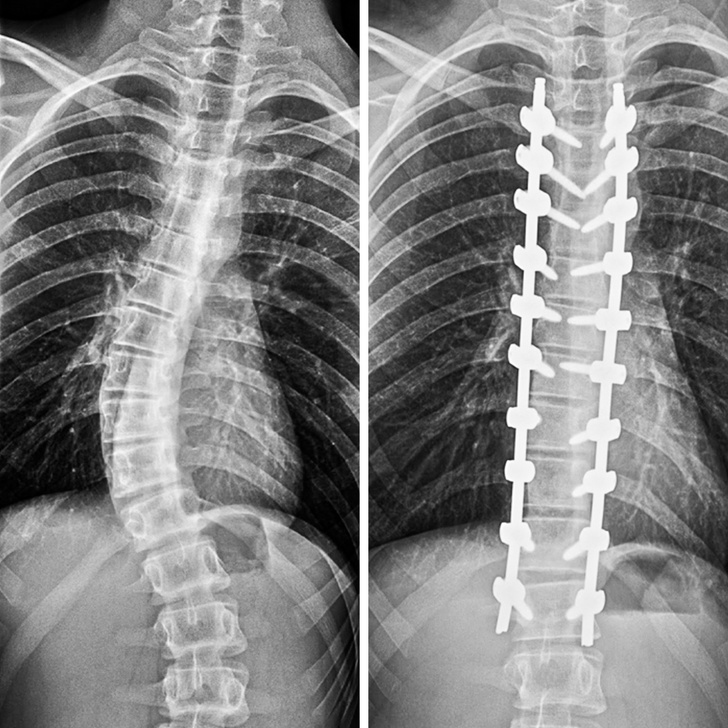

«Так виглядає мій хребет після виправлення сколіозу»